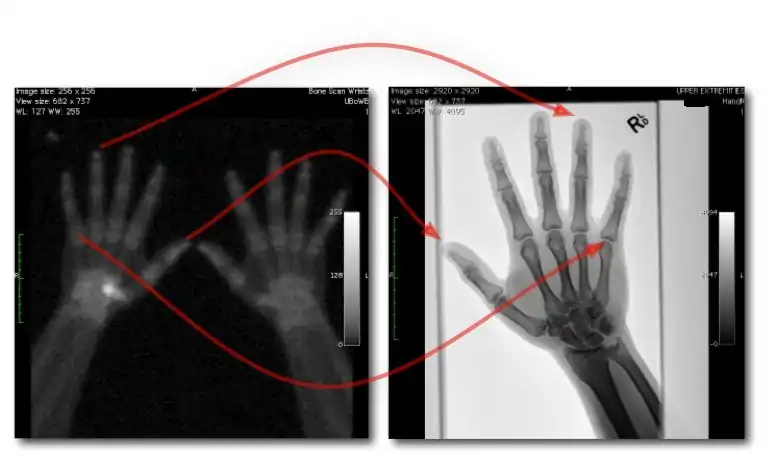

Dual-Energy Imaging

- CR and DR image receptors can generally be used for dual-energy radiography in either of two configurations:

- Dual exposures: where two separate exposures are used in applications where patient movement isn't an issue; and

- Single exposure: where two imaging plates separated by a filter are mounted in a dual-energy cassette to record the low energy image on the anterior plate and the high energy image on the other.